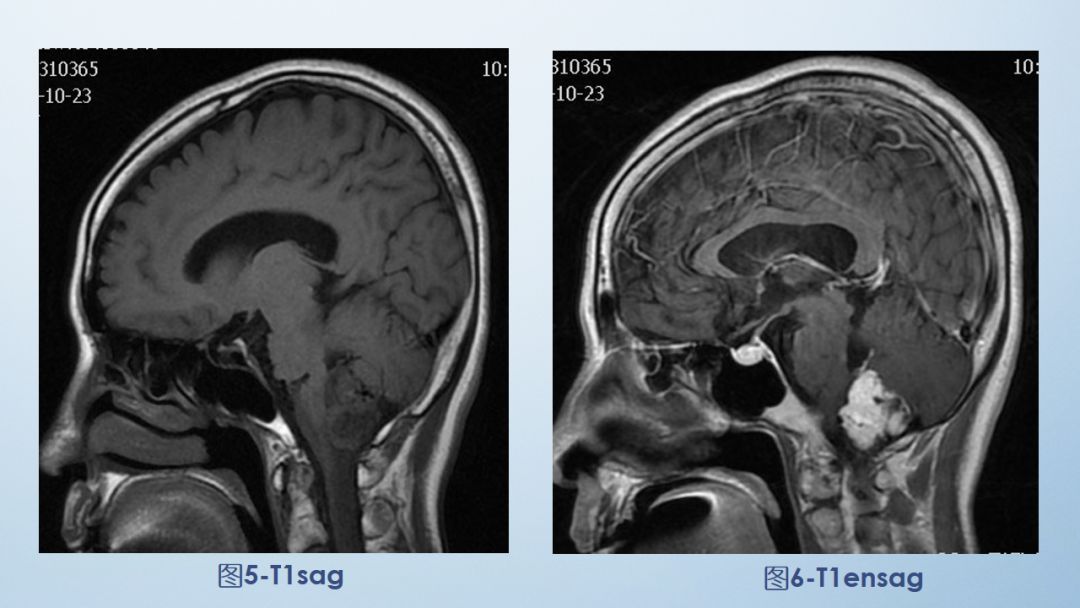

2-FLAIR

6-T1ensag

FLAIR图及T1矢状位增强:白色箭头所示小脑延髓池内可见实性占位病变,形态不规则,呈分叶状,病变边界清晰,边缘见血管流空信号影如蓝色箭头所示。

影像描述:小脑延髓池内见不规则异常信号影,呈等及稍长T1长T2信号,内部信号不均,边缘见稍粗大流空信号血管影,FLAIR病灶中心少许片状低信号,增强呈明显强化,DWI不均低信号,ADC不均高信号。小脑半球、延髓、第四脑室受压变形。临近延髓受压变窄,呈长T1长T2信号。

影像诊断:后颅窝实性占位病变,考虑实性血管母细胞瘤。